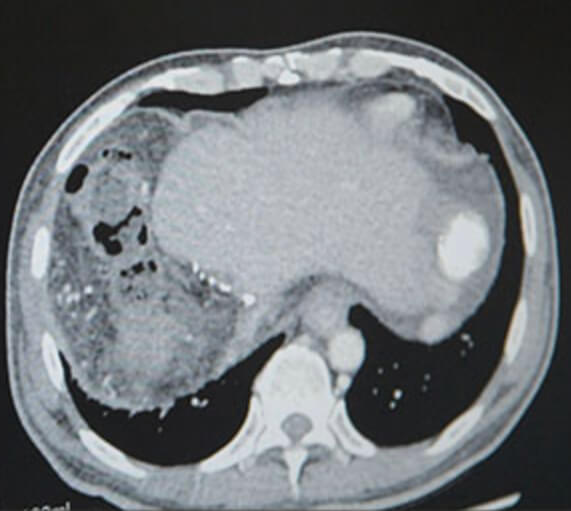

암과 2/3 이상 절제로 제 기능을 하지 못하는 간, 최근 의식을 잃어 생사를 오가는 일이 잦아졌습니다. 아빠는 아픈 딸을 챙겨주고 싶지만 오히려 보살핌을 받아야 합니다.

하루가 다르게 악화되는 아버지의 건강상태 다현이 곁에 있을 수 있는 유일한 희망은 간 이식뿐입니다. 내가 아픈 것보다 서로의 치료가 먼저라는 다현이와 아빠에게 힘이 되어 주세요.